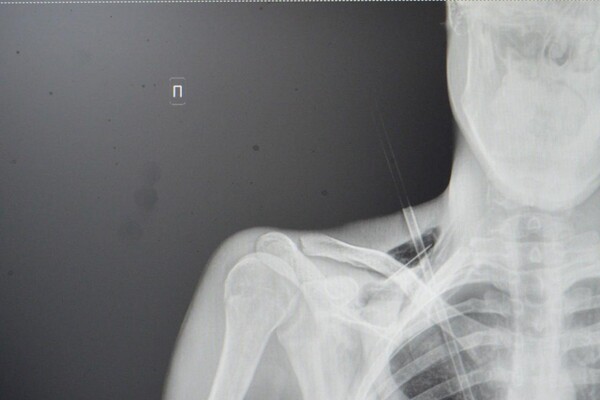

Как рассказали медики, юноша поступил в больницу на скорой со стрелой в грудной клетке. Он рассказал, что вместе с девушкой занимался стрельбой из спортивного лука, когда стрела срикошетила от дерева и вонзилась ему в грудь.

После госпитализации пациента отправили на экстренную операцию: стрела прошла между ключицей и правым ребром, пробив верхушку легкого на шесть сантиметров. По словам врачей, юноше повезло, что предмет не задел подключичную артерию или вену.

«Это привело бы к критическому кровотечению. Такие травмы требуют немедленного хирургического вмешательства. Мы успешно удалили инородное тело, а потом ушили поврежденное легкое и дренировали плевральную полость», — рассказал хирург больницы Тимур Колесников.